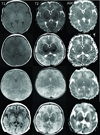

Methods: Neonates with HIE had autoregulation monitoring with the hemoglobin volume index (HVx) during therapeutic hypothermia, rewarming, and the first 6 h of normothermia. The 5-mm Hg range of mean arterial blood pressure (MAP) with best vasoreactivity (MAPOPT) was identified. The percentage of time spent with MAP below MAPOPT and deviation in MAP from MAPOPT were measured. Neonates received brain magnetic resonance imaging (MRI) 3-7 d after treatment. MRIs were coded as no, mild, or moderate/severe injury in five regions.

Results: HVx identified MAPOPT in 79% (19/24), 77% (17/22), and 86% (18/21) of the neonates during hypothermia, rewarming, and normothermia, respectively. Neonates with moderate/severe injury in paracentral gyri, white matter, basal ganglia, and thalamus spent a greater proportion of time with MAP below MAPOPT during rewarming than neonates with no or mild injury. Neonates with moderate/severe injury in paracentral gyri, basal ganglia, and thalamus had greater MAP deviation below MAPOPT during rewarming than neonates without injury.